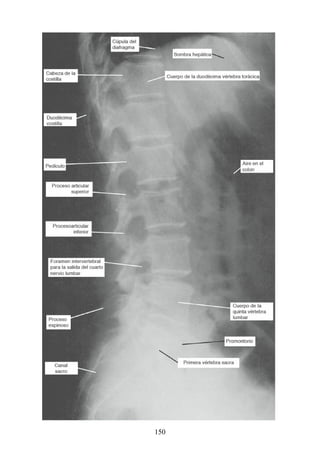

vimiento es significativa, el mesotendón desaparece o permanece en forma de

filamentos delgados, las vínculas (p. ej., en los tendones largos de los músculos

flexores de los dedos de pies y manos). Las vainas sinoviales se encuentran